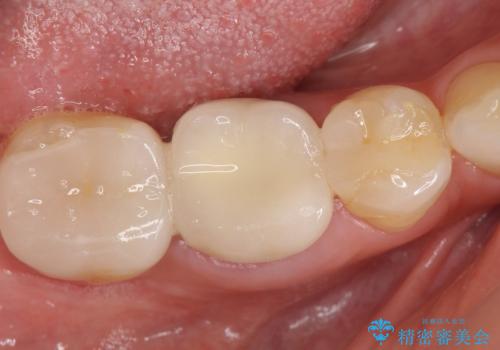

セラミックインレー 冷たいものがしみる奥歯の治療